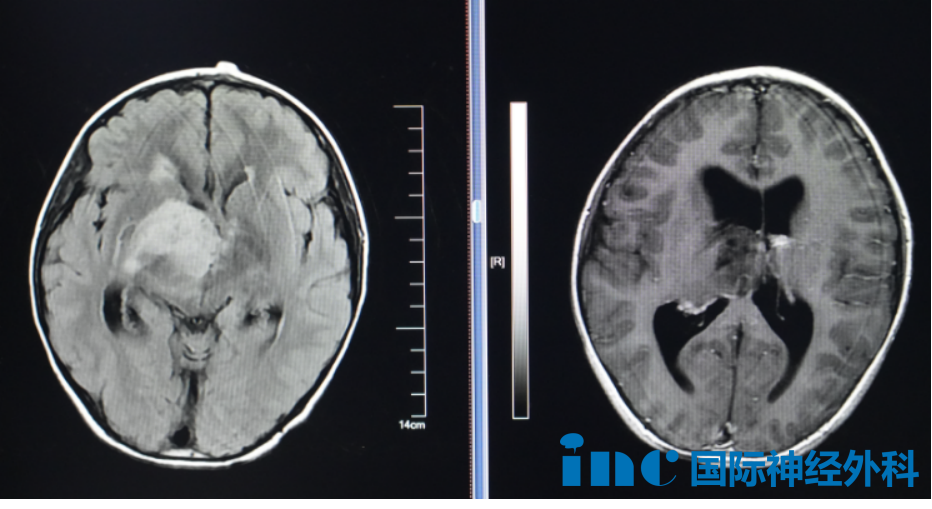

霖霖意外查出腦瘤——右側(cè)海馬、右頂葉占位沒有帶來明顯癥狀??紤]到孩子年齡太小,家人最初選擇了保守觀察。然而,這顆潛伏的“腫瘤怪獸”并未真正沉睡,它只是在暗中蓄力,伺機(jī)而動。

不到一年時間,霖霖的丘腦已被逐漸增大的腫瘤步步緊逼、推擠——露出猙獰面目的腫瘤,還能繼續(xù)觀察嗎?

影像

面對這一局面,擁有40多年神經(jīng)外科經(jīng)驗的巴特朗菲教授如何評估?

10月22日,霖霖父母帶著孩子前往蘇州大學(xué)附屬兒童醫(yī)院,與巴教授面對面交流。面對父母的疑惑,他解釋道:“這種腫瘤不會自行停止生長,一年后復(fù)查時會變大。另一個問題是,這類腫瘤可能會發(fā)生基因變化,轉(zhuǎn)變?yōu)楦鼝盒缘念愋?。而且腫瘤靠近顳葉內(nèi)側(cè)部,這一部位的腫瘤容易誘發(fā)癲癇發(fā)作……”

父母最關(guān)心的,始終是孩子未來的生活質(zhì)量。為了讓孩子盡早擺脫腫瘤的威脅,他們最終堅定地選擇了手術(shù)。